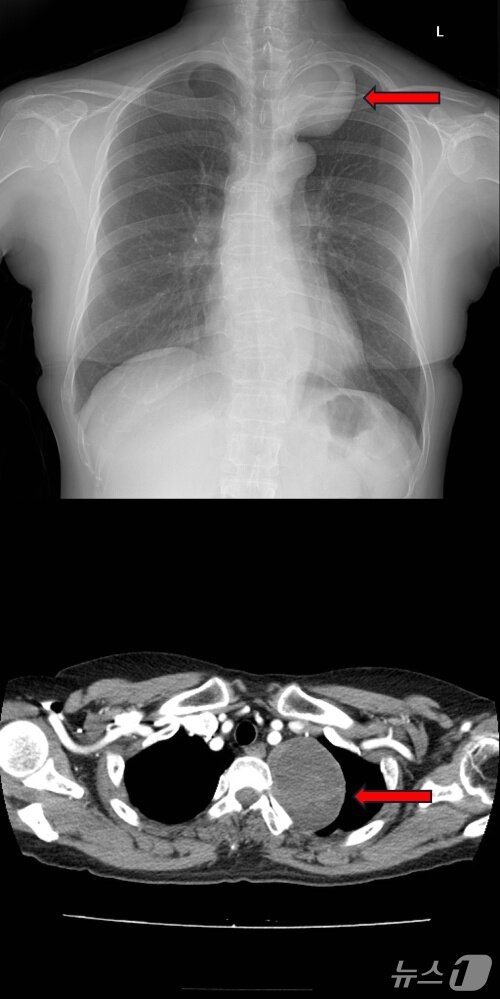

본문 이미지 - 종격동 종양 환자의 흉부 X선사진(위), 종격동 종양 환자의 흉부 CT사진(아래).(고려대학교 안산병원 제공)

종격동 종양 환자의 흉부 X선사진(위), 종격동 종양 환자의 흉부 CT사진(아래).(고려대학교 안산병원 제공)